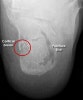

X-ray : Lover’s fracture

X-ray : Calcaneal tuberosity avulsion fracture